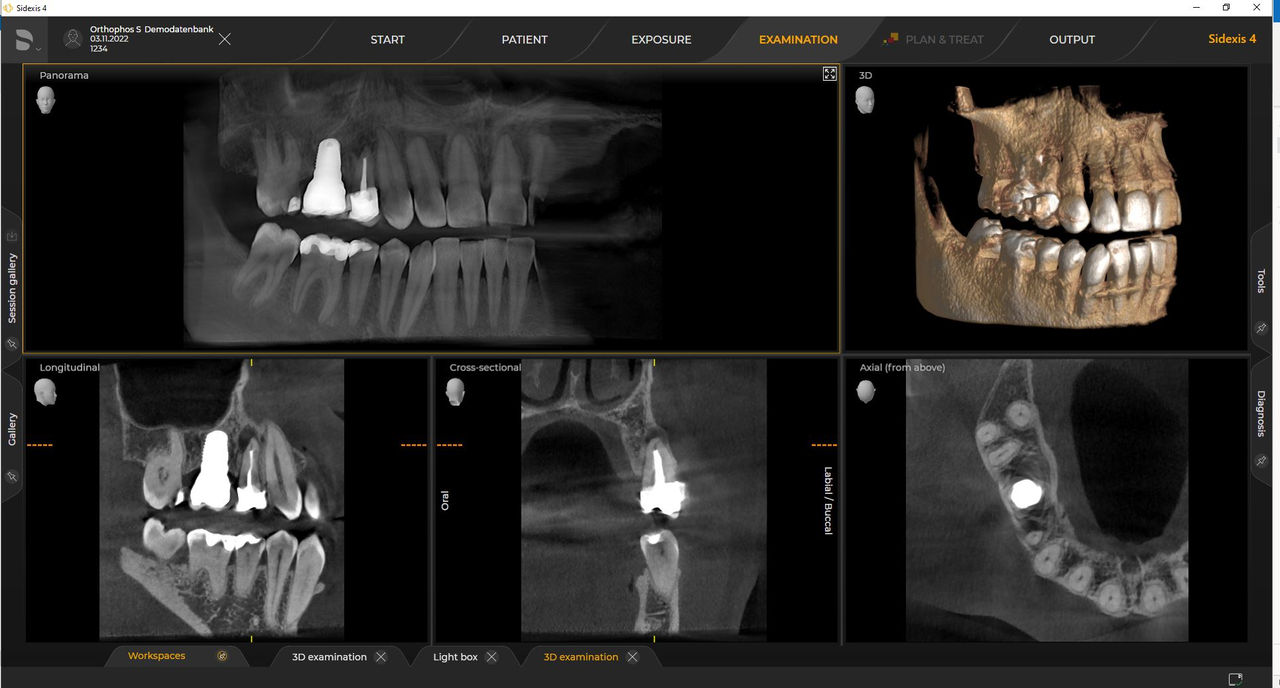

Urządzenia rentgenowskie firmy Dentsply Sirona współpracują wyłącznie z systemem Sidexis 4. Można łatwo przenieść dane z systemu Sidexis XG do systemu Sidexis 4. Sidexis 4 zapewnia pełną funkcjonalność cyfrową dzięki najnowszym narzędziom